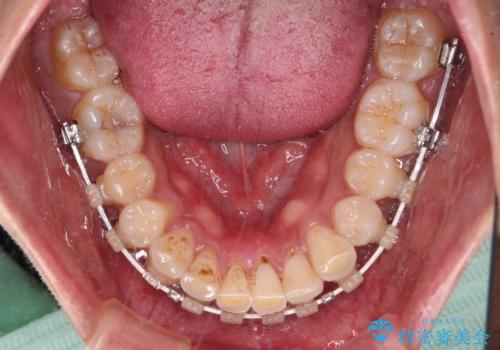

- 深い咬み合わせと前歯のデコボコを改善したいとのことで来院された患者様です。

口元の突出感はないものの、上顎前歯のデコボコが著しく、右側の咬み合わせがずれていたため、上顎右側第一小臼歯1本を抜歯することとしました。

咬合力が非常に強く、抜歯したスペースがなかなか閉じないであろうことは予想できましたが、思っていた以上に期間がかかりました。

前歯のすり減りも著しかったため、仕上げの位置の調整にも期間を要しました。